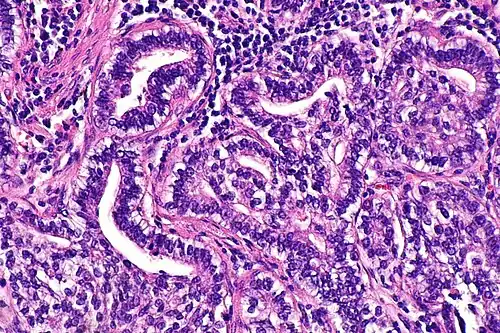

Micrograph showing fetal adenocarcinoma. H&E stain.

Fetal adenocarcinoma (FA) of the lung is a rare subtype of pulmonary adenocarcinoma that exhibits tissue architecture and cell characteristics that resemble fetal lung tissue upon microscopic examination. It is currently considered a variant of solid adenocarcinoma with mucin production.[1]

FA is an epithelial tumor whose cells and architecture resemble that of fetal lung tissues in the pseudoglandular stage of development (which occurs at about 10–16 weeks gestation in the human),[6] with complex glandular structures and morules with cell nuclei that appear clear due to the accumulation of biotin.[15]